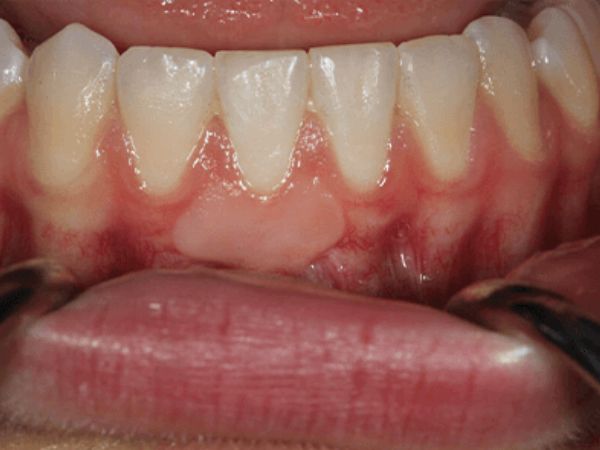

Before gum treatment Before

After gum treatment After